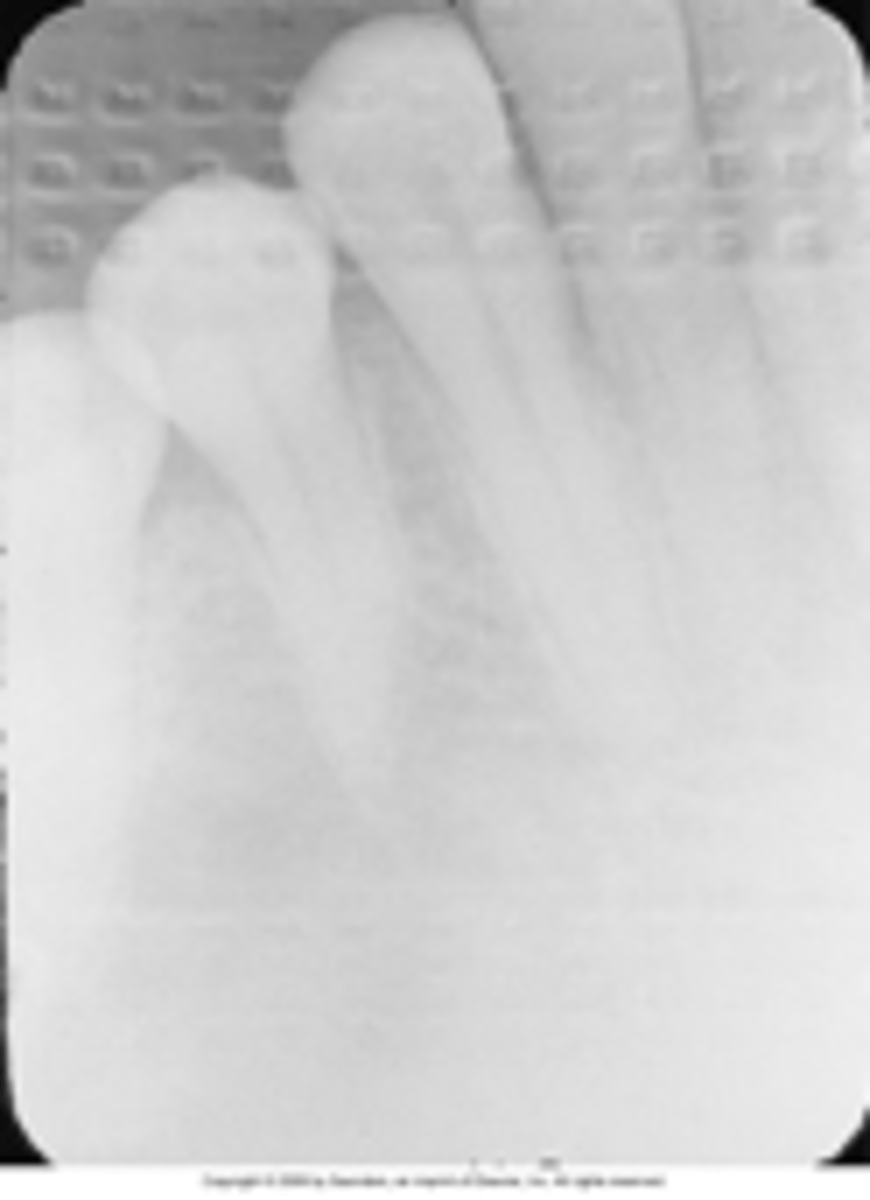

Overdeveloped image

overdeveloped film

Overexposed film